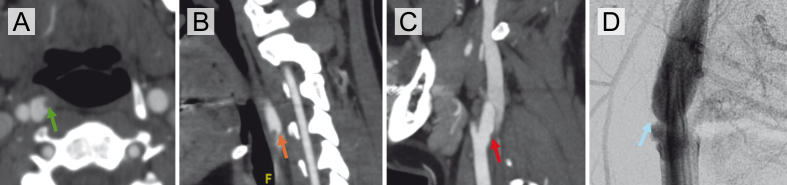

Background: Carotid artery webs (CWs) are an underrecognized cause of ischemic stroke, particularly in younger patients who lack conventional vascular risk factors. CWs are thought to represent an intimal variant of fibromuscular dysplasia (FMD); however, histopathologic data supporting this hypothesis remain limited. We report a case series of three patients with CW-related ischemic stroke who underwent carotid endarterectomy (CEA), allowing for histological analysis of the resected specimens. Methods: We retrospectively reviewed patients admitted to a Comprehensive Stroke Center between January 2015 and April 2025 with ischemic stroke or transient ischemic attack attributed to an ipsilateral carotid web who subsequently underwent carotid endarterectomy. Clinical data, imaging findings, and histopathologic features were analyzed. All cases met criteria for embolic stroke of undetermined source (ESUS) prior to surgery. Results: Three patients with CW-related stroke underwent carotid endarterectomy following recurrent events or high embolic risk. In two cases, superimposed thrombi led to initial misdiagnoses such as soft plaque or dissection. Histopathologic analysis consistently demonstrated fibrovascular tissue with intimal fibroid hyperplasia and myxoid degeneration, without lipid-rich plaques or inflammatory infiltrates. No patients experienced recurrent stroke or TIA by the time of their last documented follow-up. Conclusions: CWs represent a distinct non-atherosclerotic pathology characterized by intimal hyperplasia and myxoid degeneration. Superimposed thrombus may complicate diagnosis, often mimicking plaque or dissection. Advanced imaging, including MR vessel wall imaging and intravascular optical coherence tomography (OCT), can aid in accurate identification. Carotid revascularization may be effective in selected patients, particularly those with recurrence or ESUS. Prospective studies are needed to inform standardized diagnostic and therapeutic strategies.